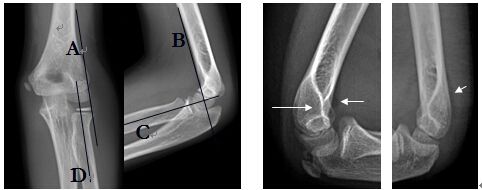

因肘部創(chuàng)傷性關(guān)節(jié)炎而出現(xiàn)尺神經(jīng)受壓,在尺側(cè)腕屈肌兩頭之間有一增厚的纖維帶,壓迫尺神經(jīng),稱之為肘管綜合征。在肱骨內(nèi)上髁與尺骨鷹咀之間有一弧形窄而深的骨溝,有深筋膜橫架于上,形成一骨性纖維鞘管,即尺神經(jīng)溝,也稱肘尺管。管內(nèi)為尺神經(jīng)及尺側(cè)上副動、靜脈。